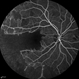

- capillary closure, macular infarction

- Wide-field FA image of the left eye of a 28-year-old woman with idiopathic occlusive retinal vasculitis 6 months after the onset.